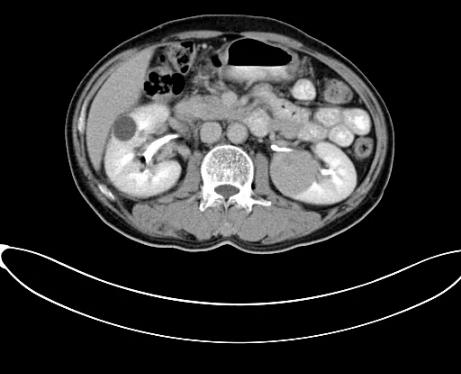

據(jù)安圖叔叔的兒子回憶道,安圖叔叔在體檢前沒有發(fā)現(xiàn)任何不適的癥狀,在體檢后才知雙腎占位,右腎下級占位16.1*7.2cm,左腎下級腫瘤約3.7*4.3cm的情況。突如其來的病情讓一家人陷入了恐慌,從未想過一個健康自律的人會突然間就被檢出腎癌,還是雙腎。安圖叔叔的兒子激動地說道:“我當時一下子懵了,父親之前表現(xiàn)那么健康,一查竟病得很重,為確診我把父親轉(zhuǎn)接到新加坡就診,那邊的醫(yī)生在看了我父親的片子后都表示這是腫瘤,要做切除雙腎然后再透析,對于我們來說,切腎這樣的治療方案對我們來說是無法接受的,父親畢竟一把年紀,這樣做法太傷他身體。”

2017年9月安圖叔叔開啟新治療之路,入院檢查發(fā)現(xiàn)安圖叔叔右腎透明細胞癌T3NxM1IV期、左腎癌、縱隔淋巴結(jié)轉(zhuǎn)移瘤。為緩解安圖叔叔腰疼的狀況,9月21日進行介入治療。經(jīng)復(fù)大專家認真探討后,考慮到安圖叔叔身體精神狀態(tài)良好,可進行冷凍消融術(shù)。經(jīng)專家解說和安慰后,安圖一家懸著心終于放下了。

2017年9月29日,從CT影像看到右腎情況更為嚴重。為減緩腫瘤增長的速度,專家進行商議后,最終決定由牛立志教授主刀為安圖叔叔進行了右腎腫瘤冷凍消融術(shù)。手術(shù)開始后,牛立志教授在CT和超聲引導(dǎo)下,同時使用兩根冷凍針固定病灶,精準滅活腫瘤;術(shù)后很成功無不良反應(yīng)。術(shù)后一周進行第二次雙腎腫瘤冷凍消融術(shù)。安圖叔叔兒子笑道:“當時真的很緊張,醫(yī)生勸慰我無須擔(dān)心,都交給他們,我們都很清楚知道父親的病情,真的很感謝也很慶幸我父親遇到復(fù)大的醫(yī)護人員,免受開刀之痛。住院期間醫(yī)護人員很盡心盡力的照顧父親,手術(shù)的成功離不開他們的辛勞付出。”